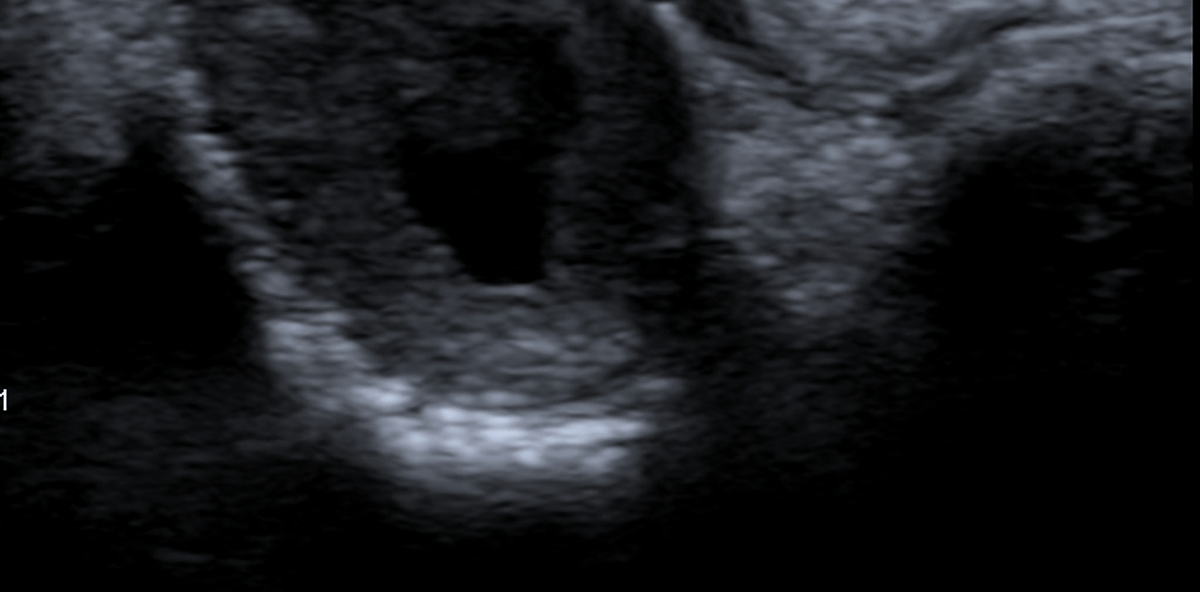

Im OPG (Abb. 1) sieht man einen osteolytischen Prozess im Bereich der Zahnwurzel des Zahnes 21, die als relativ große apikale Parodontitis bezeichnet wurde. Die Aufhellung hat einen Durchmesser von circa 1cm, und im Röntgenbild scheint es so, als ob die Wurzel des Zahnes 22 ebenfalls betroffen ist. Zum besseren Verständ-nis der sonografischen Untersuchung wurde auf einem Schädelmodell die Ultraschallsonde entsprechend dem Patientensitus appliziert. Zur einfa-cheren Orientierung wurde im Modell der Zahn 22 entfernt, sodass die Al-veole gut sichtbar ist (Abb. 2). Die sonografische Aufnahme zeigt einen relativ gut begrenzten Bereich, der in der Peripherie von einem homogenen reflexreicheren Gewebe gebildet wird. Zentral zeigt sich eine echoarme Struktur. Nach dorsal ist eine deutliche Schallverstärkung sichtbar. Es handelt sich um ein typisches sonografisches Bild einer Kieferzyste mit Flüssigkeitsansammlung (Abb. 3). In der Abbildung 4 sieht man den gleichen Situs, mit einer etwas andere Angulation der Ultraschallsonde. Dadurch erscheint zentral in der Kieferzyste eine weißliche, reflexreiche Struktur. Hierbei handelt es sich um Anteile der Zahnwurzel des Zahnes 21. Nach Auswertung der Bilder wurde eine Zystektomie mit gleichzeitiger Wurzelspitzenresektion und Wurzelfüllung vorgenommen. Im Operationssitus zeigte sich eine Ausdehnung der Zyste nach kranial und palatinal. Da der Zahn 21 ausreichend stabil im Knochen stand, konnte auf eine zusätzliche Schienung des Zahnes verzichtet werden.